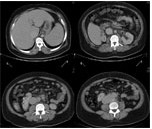

腹部CT扫描(图2)显示,其腹主动脉边缘不清,腹主动脉周围有富含血管的肿瘤、肝脏瘀血、脾肿大、右肾旋转异常。心脏超声检查发现,心脏4个腔室均扩张,心肌向心性肥厚,合并中度肺动脉高压。

图2 腹部CT扫描显示,腹主动脉的边缘不清,周围有富含血管的肿瘤。下腔静脉扩张、肝脏瘀血、 脾肿大、 右肾旋转异常。